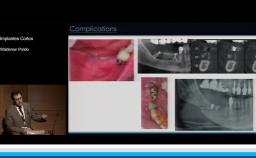

Se discuten aspectos fundamentales de los tejidos duros y blandos para obtener resultados predecibles en los casos de instalación inmediata de implantes en alvéolos post extracción (Tipo 1), centrándose en los riesgos y la necesidad de cuidadoso diagnóstico y plan de tratamiento.

evaluar los factores de riesgo estético con implantes inmediatos